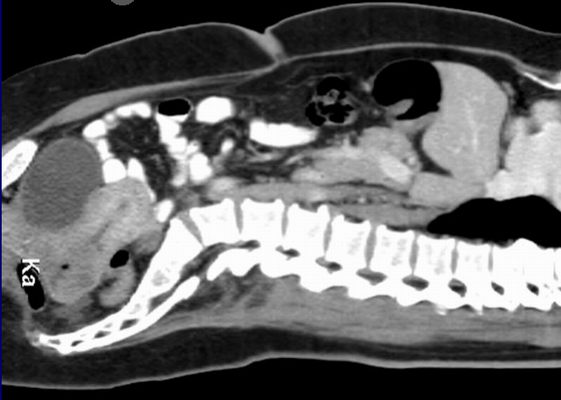

Das CT zeigt einen Längsschnitt einer Frau mit einem Zervix - Karzinom

CT sagital